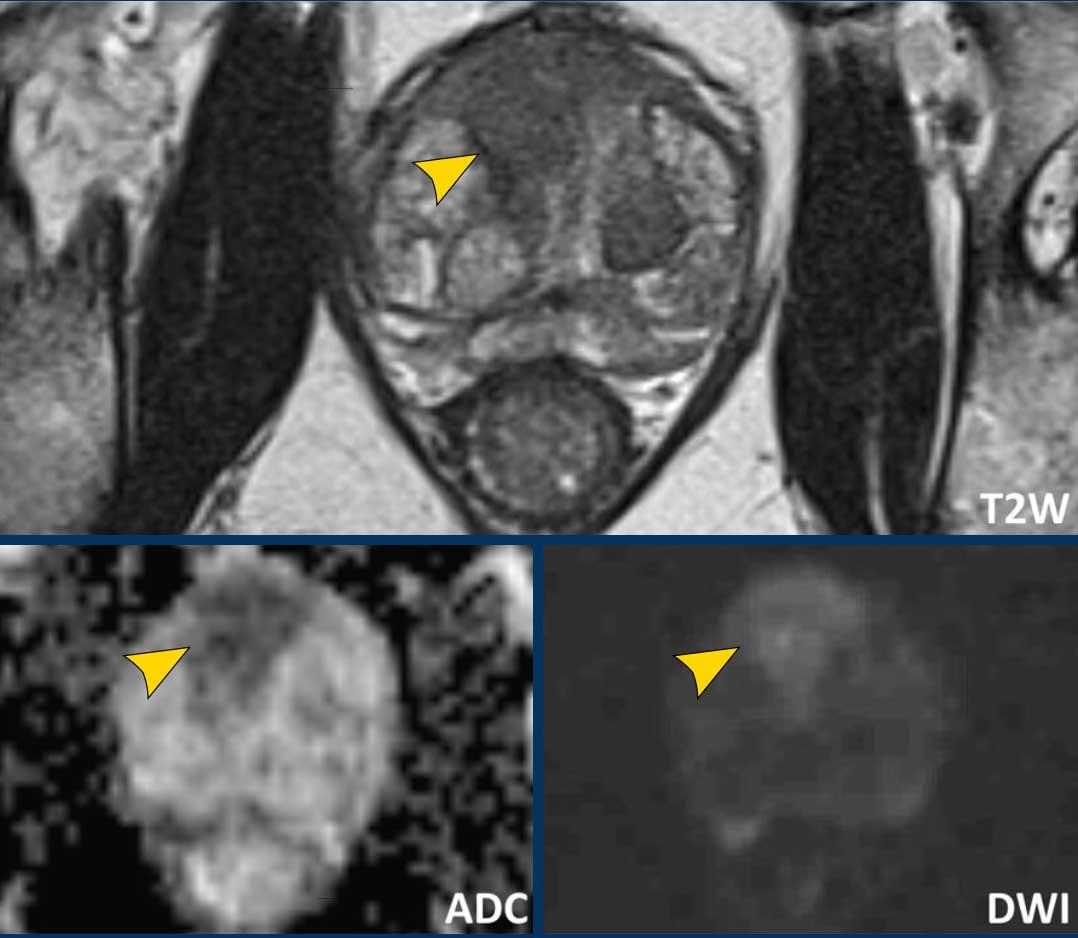

Một tổn thương kích thước 16 mm (không hiển thị phép đo) được phát hiện, nằm ở phía sau vùng ngoại vi của phần giữa tuyến tiền liệt bên phải.

Tổn thương này được xếp vào phân loại PI-RADS 5, dựa trên giảm tín hiệu rõ rệt trên ADC và tăng tín hiệu rõ rệt trên DWI (điểm 5 – chuỗi xung chính), đối chiếu với giảm tín hiệu rõ rệt trên chuỗi xung T2W (điểm 5).

Điểm Gleason là 3+4, cho thấy nguy cơ trung bình của một ung thư có tính xâm lấn cao.

Tổn thương không tiếp xúc với vỏ bao giả và không có dấu hiệu xâm lấn ra ngoài tuyến tiền liệt.